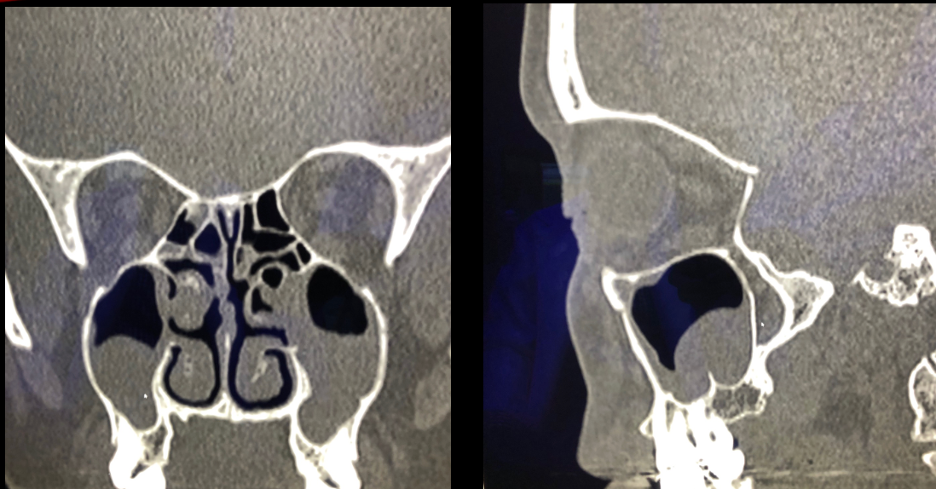

Q

A

IMAGEN OCUPACIÓN DE 95% HEMOGÉNEA SENO MAXILAR

OTRO SENO IMAGEN DE OCUPACIÓN 60%

LOS SENOS ETMOIDALES TAMBIÉN ALTERADOS. SEPTUM DESVIADO EN LA DERECHA.

PALADAR ASIMÉTRICO: DATOS DE RESPIRADOR BUCAL CRÓNCO